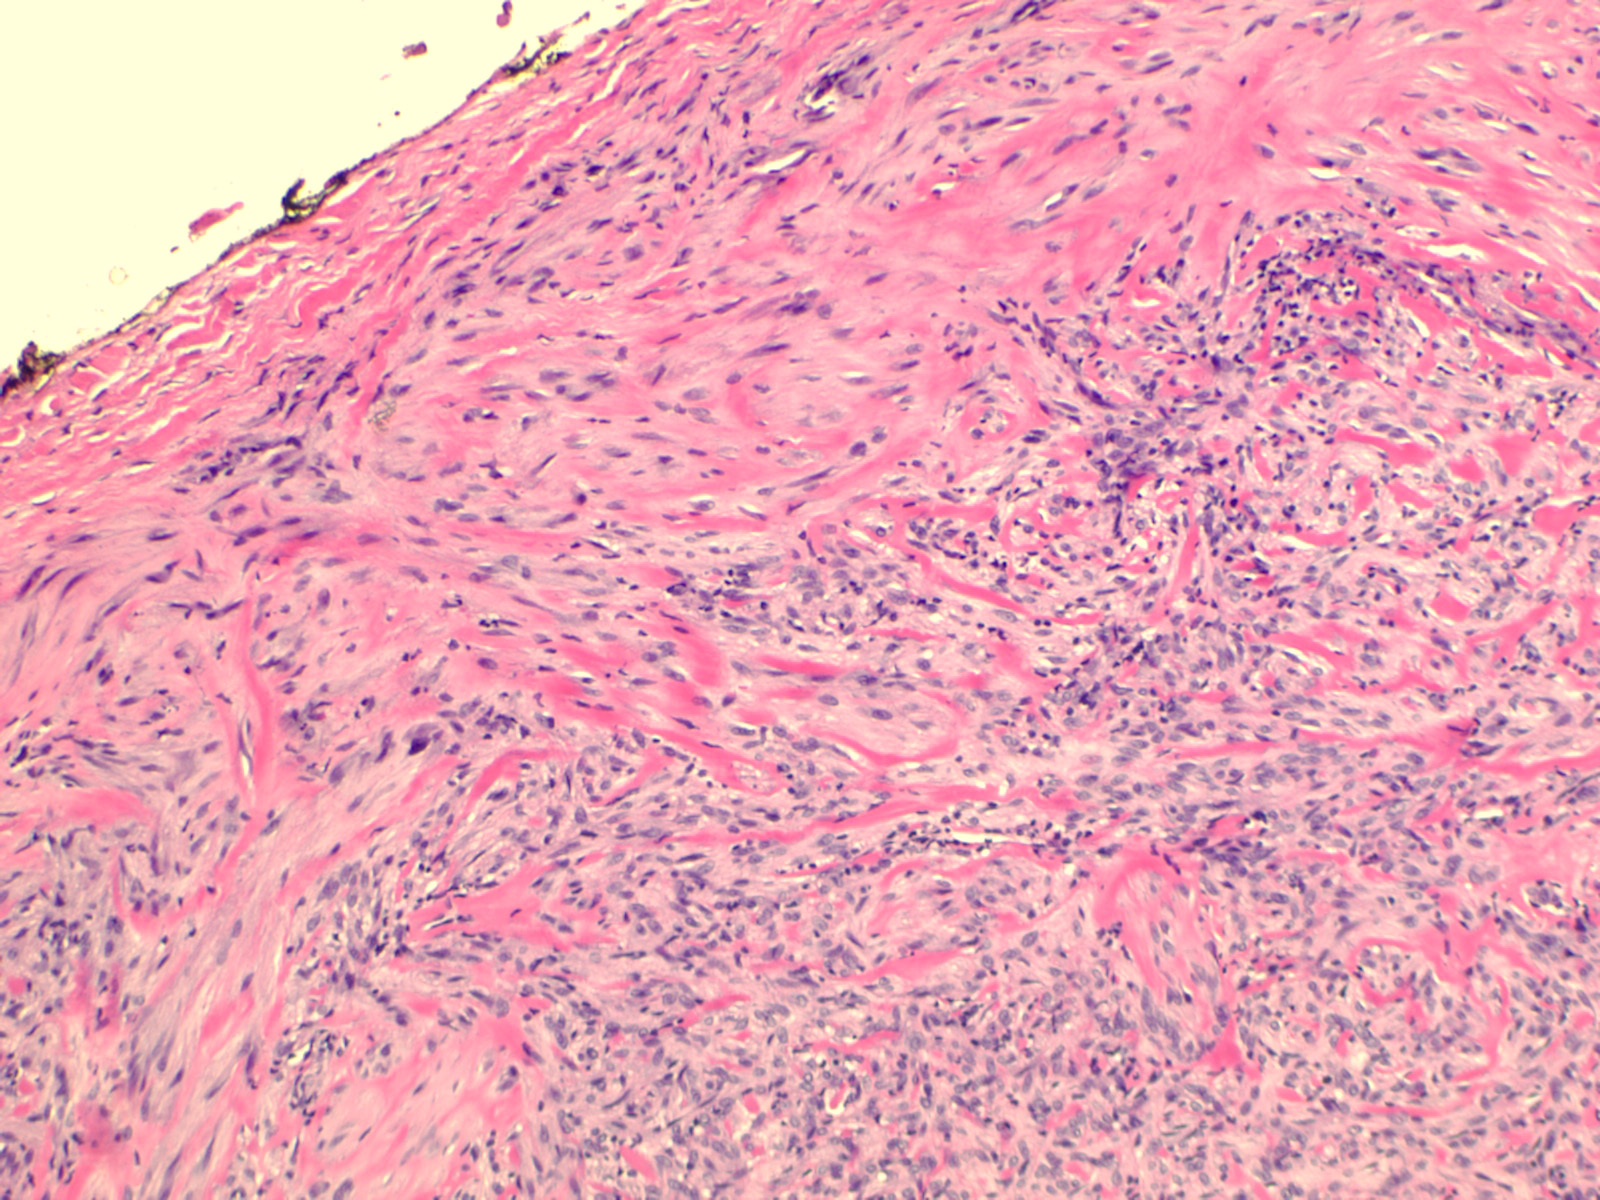

Myofibroma = الورم الليفي العضلي